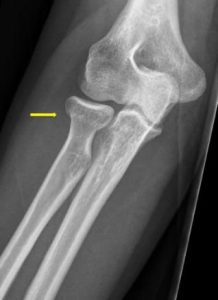

Radial head or radial neck fracture (Folder)

You have a small fracture of the head or neck of your radius, which is one of the bones in your elbow. We treat this fracture with a pressure bandage and a sling.

- You have a small fracture of the radius bone at the level of the elbow.